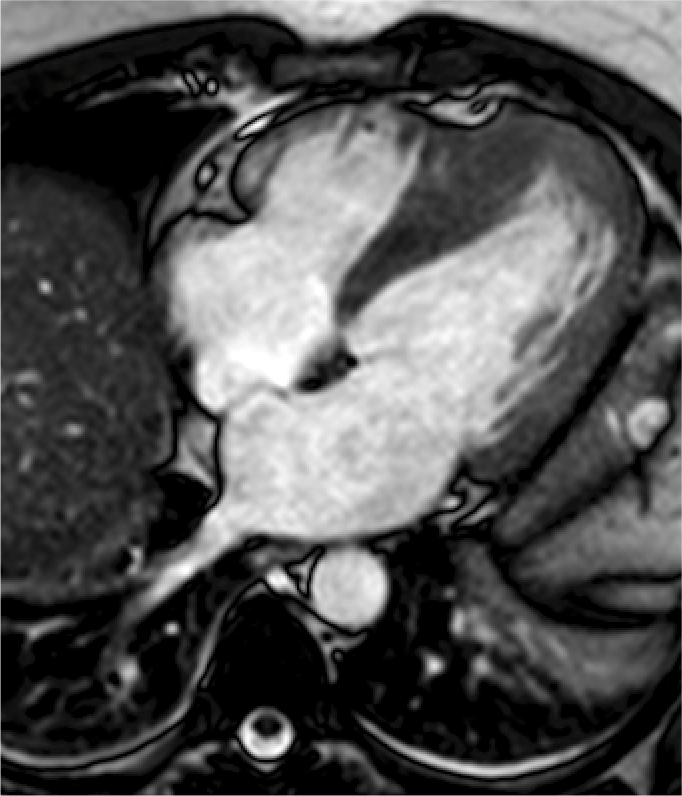

Resonancia magnética cardiaca

La resonancia magnética cardiaca es un una técnica de imagen que permite estudiar detalladamente y en una sola exploración la función y la estructura del corazón. Este auxiliar diagnóstico utiliza un potente campo magnético, sin radiación, para generar imágenes detalladas de las estructuras del corazón.

La resonancia magnética esta indicada en la evaluación de las cardiopatías congénitas tanto en el niño como en el adulto, en la evaluación de la perfusión miocárdica (resonancia cardiaca con gadolinio), de la función cardiaca, de las enfermedades del músculo cardiaco (miocardiopatías), tumores del corazón y del tejido que rodea al corazón (pericardio).

Este estudio es bien tolerado por la mayoría de las personas. El campo magnético no es dañino, pero puede causar el mal funcionamiento de algunos dispositivos médicos. La mayoría de los implantes ortopédicos no presentan riesgos, pero siempre debes informar al técnico de resonancia magnética si tiene algún dispositivo o metal en su cuerpo.